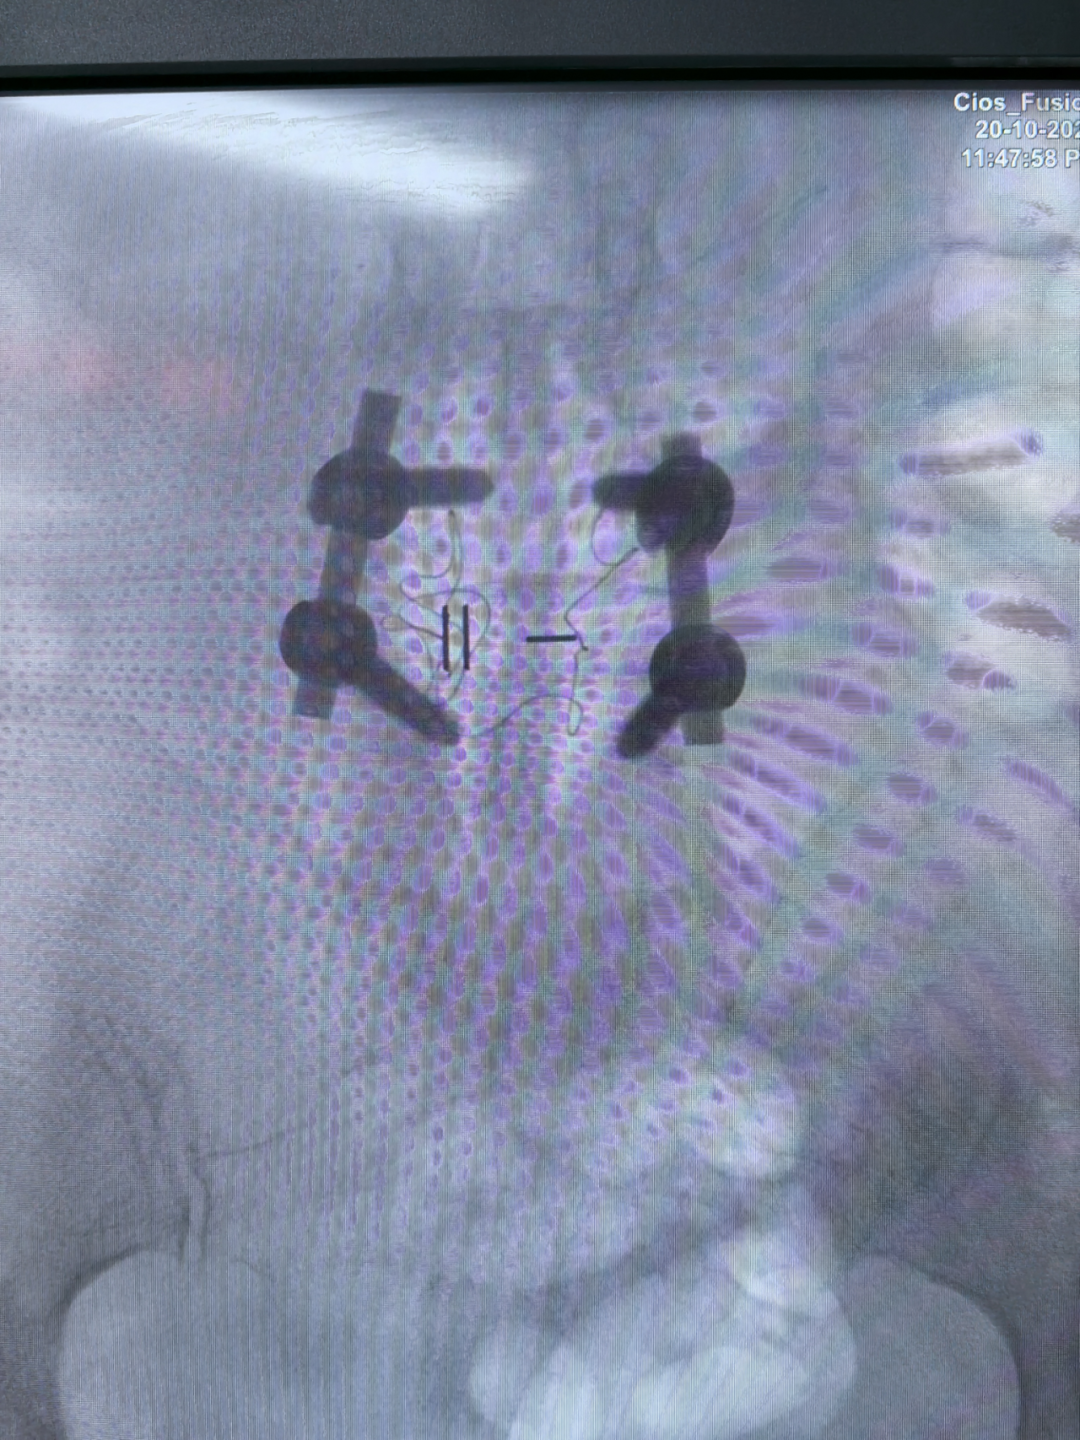

腰4-5减压植骨融合内固定术